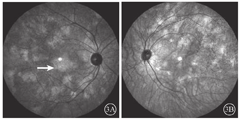

患者女,51岁,因左眼视力下降6年于2018年1月15日到吉林大学第二医院眼科就诊。否认相关既往史及家族史。患者颜面部及上肢可见多个神经纤维瘤及咖啡斑(图1)。眼科检查:右眼、左眼矫正视力分别为1.0、0.15。双眼虹膜见Lisch结节(图2),其余眼前节正常。眼底彩色照相、FAF及FFA检查,双眼均未见异常。红外眼底成像检查,双眼后极部多发片状强反射病灶(图3)。OCT增强深度成像(EDI-OCT)检查,与红外眼底成像强反射病灶对应处脉络膜毛细血管层反射增强(图4)。ICGA检查,早期可见与红外眼底成像强反射病灶相对应处呈弱荧光,随着时间延长,中晚期弱荧光面积逐渐缩小直至消失(图5)。诊断:Ⅰ型神经纤维瘤病。

Ⅰ型神经纤维瘤病大多存在脉络膜结节,常规眼底检查和眼底彩色照相不能发现病变[5]。本文例2患者仅在彩色眼底像中可见双眼黄斑区末梢血管略扭曲,这样的异常血管只存在于视网膜浅层,常见于颞上、颞下静脉的二三级分支,且在FFA上无荧光素渗漏;在EDI-OCT上可见对应位置的脉络膜毛细血管层萎缩以及脉络膜大血管缺失。但脉络膜大血管在解剖结构上是缺失还是仅仅被压缩,尚无定论。对于这样的脉络膜结节,最有效的检查手段是红外眼底成像。这些脉络膜结节由包绕神经纤维轴突增生的施万细胞和黑色素细胞组成,由于黑色素细胞对红外线的反向散射作用,病灶在红外眼底成像上表现为强反射。另外,脉络膜结节的致密结构降低了可吸收红外线的血红蛋白和水等血液成分的含量,病变区域红外线吸收得相对减少也是红外眼底成像上反射增强的原因之一[6]。